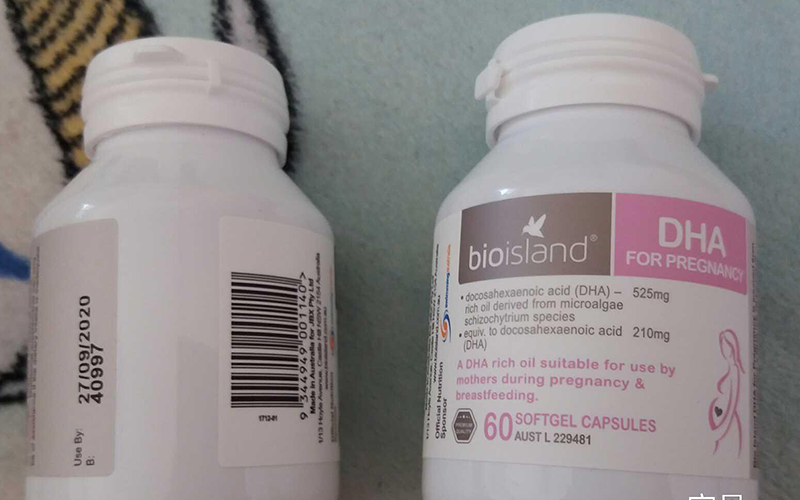

为什么很多医院不开dha给孕妇吃?

很多医院不开dha给孕妇吃是因为DHA虽是比较好的保健品,但并不是每一个孩都子都需要补充DHA,也不是...

很多医院不开dha给孕妇吃是因为DHA虽是比较好的保健品,但并不是每一个孩都子都需要补充DHA,也不是...